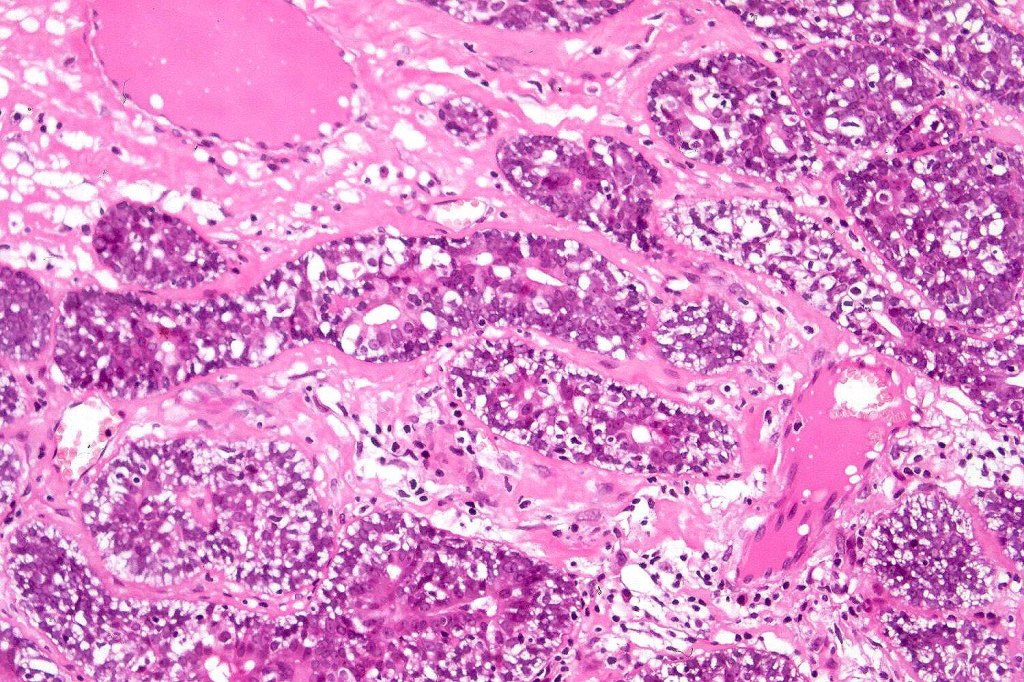

Histological features

•Pre-existent spiradenoma

•Malignant component shows loss of dual cell population, increased mitotic activity, atypical mitoses & necrosis

•Perineural infiltration & LVI may be present